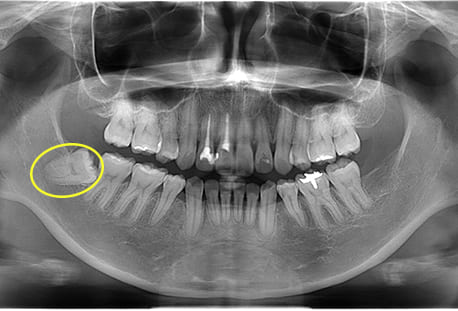

Case09

- 下顎左の水平埋伏智歯

- 治療内容

- 下顎左の水平埋伏智歯を抜歯したケースです。

<リスク・副作用>

手術後は痛み、腫れ、痺れなどの副作用が生じる場合があります。